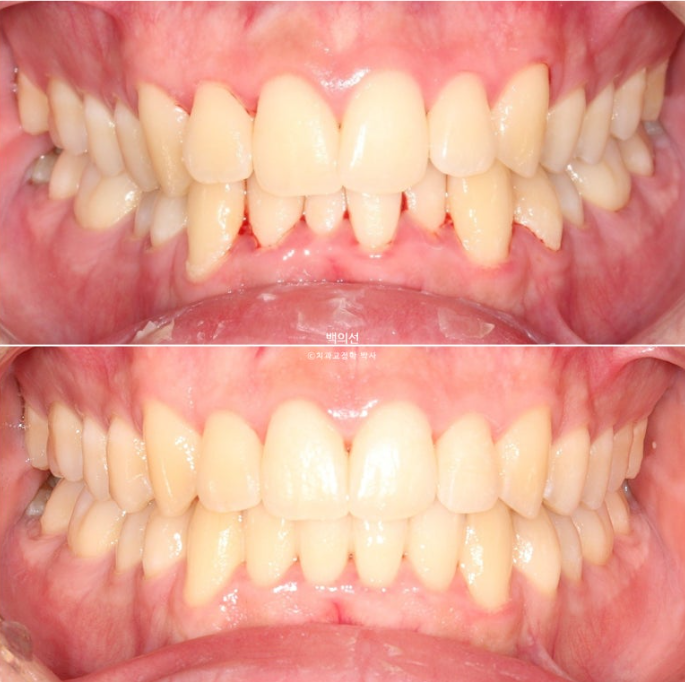

이제 전후 비교 보겠습니다.

25.02~25.08

아래 앞니의 배열 개선이 드라마틱 하네요. 안으로 쓰러진 작은어금니들 배열도 좋습니다.